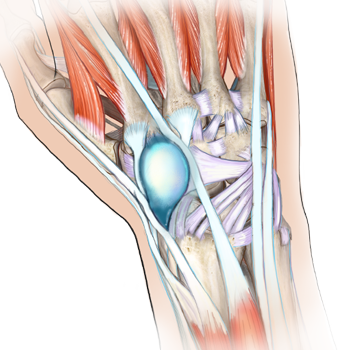

Ligaments / Ganglia

Camp 2

1.0 ECMECs

Acquire a good knowledge of ligaments and ganglia